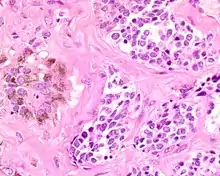

The tumor is usually very well circumscribed but not encapsulated. There are two cell types present (biphasic), arranged in alveolar or tubular configurations.

A high power of melanotic neuroectodermal tumor of infancy showing pigmented large epithelioid cells and smaller primitive cells (hematoxylin and eosin stain).

There are centrally located, small, darkly staining cells comprising the majority of cells. These cells have a fibrillary cytoplasm surrounding round nuclei with coarse and heavy nuclear chromatin. These cells are surrounded by much larger polygonal cells that have open nuclear chromatin and abundant opaque cytoplasm that has granular melanin pigment.

A high power of melanotic neuroectodermal tumor of infancy showing pigmented large epithelioid cells and smaller primitive cells in alveolar nests (hematoxylin and eosin stain).

There is usually no hemorrhage, necrosis or increased mitoses.[1][4]